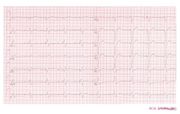

| 00:20, 6 August 2012 | Ddd paced 12lead.jpg (file) |  |

73 KB | 1 | |